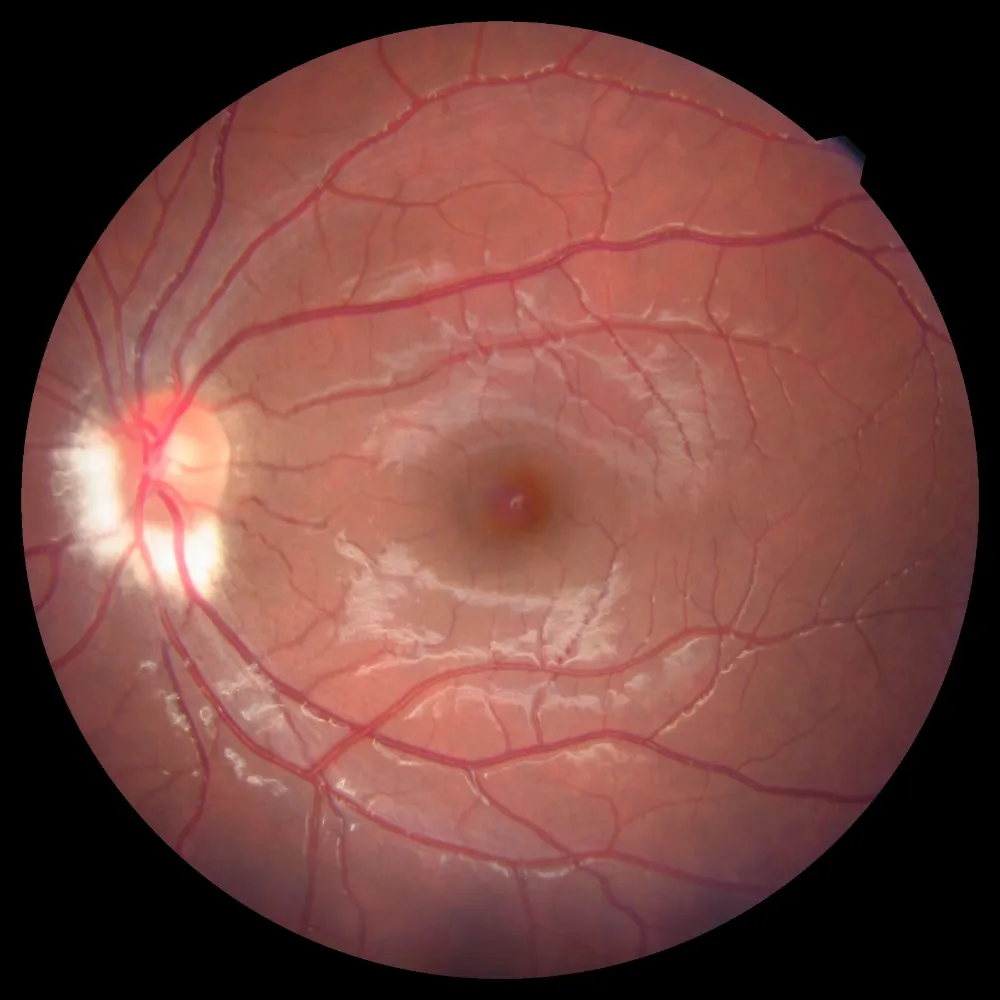

Gölcük Necati Çelik Devlet Hastanesi, göz sağlığı hizmetlerinde tanı ve takip süreçlerini güçlendirmek amacıyla Optik Koherens Tomografi (OCT) cihazını hizmete sundu. Yeni cihaz sayesinde retina, optik sinir, kornea ve ön segment yapıları mikron düzeyinde incelenebilecek; hastalara daha hızlı, güvenilir ve konforlu bir muayene deneyimi sağlanacak.

OCT teknolojisi, gözün hem arka (retina, makula, optik sinir başı) hem de ön segment (kornea, ön kamara) yapılarının temassız ve ağrısız şekilde görüntülenmesine olanak tanıyor.

Bu sayede glokom, diyabetik retinopati, makula dejenerasyonu gibi hastalıkların erken evrede tespiti mümkün hale gelirken, hastaların tedavi süreçleri daha etkin biçimde takip edilebilecek.